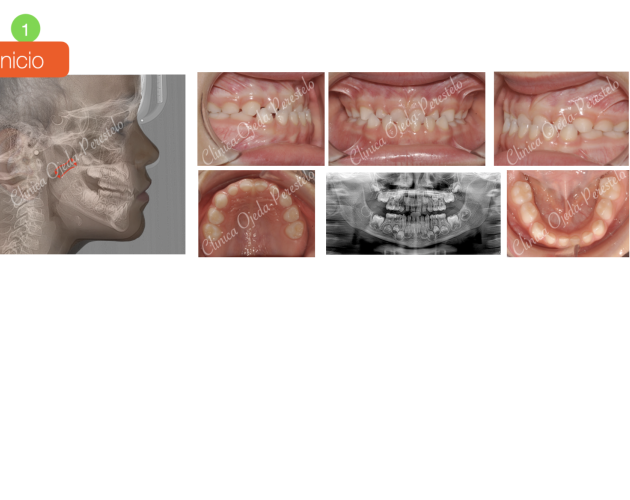

Mordida Abierta de molar a molar Casos de Éxito - Adultos

Clase II esquelética con Cirugía de Avance Md Casos de Éxito - Ortodoncia Plástica (Invisalign/Angel) - Adultos

Asimetría Facial en Clase III ósea y C.Ortognática Casos de Éxito - Mordida Cruzada - Adultos - Cirugía Ortognática

Clase III esquelética en dentición temporal Casos de Éxito - Niños

Clase II esquelética en niño con apnea moderada Casos de Éxito - Niños

Caso Ortodoncia Lingual Superior con Vestibular Inferior Casos de Éxito - Ortodoncia Lingual

Caso Multidisciplinar: Ortodoncia- Coronas sobre Implantes Casos de Éxito - Adultos - Casos Multidisciplinares

Caso Multidisciplinar: Ortodoncia-Implantes-Pónticos-Bioestética Casos de Éxito - Adultos - Casos Multidisciplinares

2ºMolar Mandibular Retenido Casos de Éxito - Dientes Retenidos

Caso Multidisciplinar: Ortodoncia-Implantes-Bioestética 11-21 Casos de Éxito - Casos Multidisciplinares

Caninos Maxilares Retenidos (13-23) + Bioestética 21-22 Casos de Éxito - Niños - Dientes Retenidos - Casos Multidisciplinares

Premolar Mandibular Retenido (35) Casos de Éxito - Niños - Dientes Retenidos

Clase II con Mordida Abierta Casos de Éxito - Ortodoncia Plástica (Invisalign/Angel) - Adultos

Clase II severa en Mandíbula Hipoplásica Casos de Éxito - Adultos - Cirugía Ortognática

Expansión Maxilar Asistida en Mord.Cruzada Casos de Éxito - Mordida Cruzada - Adultos - Cirugía Ortognática

Mordida Cruzada Unilateral con Apiñamiento Severo Casos de Éxito - Mordida Cruzada - Adultos

Mordida Cruzada Bilateral Casos de Éxito - Mordida Cruzada - Niños

Clase III esquelética en dentición definitiva Casos de Éxito - Niños

Mordida Cruzada con dolor Craneofacial Casos de Éxito - Ortodoncia Plástica (Invisalign/Angel) - Mordida Cruzada - Adultos

Clase III ósea severa con C.Ortognática Casos de Éxito - Mordida Cruzada - Adultos - Cirugía Ortognática

Asimetría Facial en Clase III ósea y C.Ortognática Casos de Éxito - Mordida Cruzada - Adultos - Cirugía Ortognática - Casos Multidisciplinares

Biprotusión esquelética con Sonrisa Gingival Casos de Éxito - Adultos - Cirugía Ortognática

Clase II osea de causa Md con Cara Larga Casos de Éxito - Adultos - Cirugía Ortognática

Clase II ósea con Resalte muy Aumentado y Extracciones dentarias Casos de Éxito - Adultos - Casos Multidisciplinares

Apiñamiento severo con molares con mal pronóstico Casos de Éxito - Adultos

Mordida Abierta Posterior con M. Cruzada en clase III ósea Casos de Éxito - Mordida Cruzada - Adultos

Clase III ósea tratada con Exo de cordales y Microtornillos Casos de Éxito - Mordida Cruzada - Adultos

Clase II con apiñamiento y sobremordida severa Casos de Éxito - Ortodoncia Plástica (Invisalign/Angel) - Adultos

Sonrisa gingival (encías) con Resalte Aumentado Casos de Éxito - Mordida Cruzada - Adultos

Clase III esquelética en dentición mixta Casos de Éxito - Niños

Canino Mandibular Retenido (33) Casos de Éxito - Dientes Retenidos

Mordida Cruzada y Abierta severa Casos de Éxito - Mordida Cruzada - Adultos

Ortodoncia-Implantes-Bioestética 22 Casos de Éxito - Ortodoncia Plástica (Invisalign/Angel) - Adultos - Casos Multidisciplinares

C Multidisciplinar: Orto Plástica + MASPE+ Corticotomías + Regen Casos de Éxito - Ortodoncia Plástica (Invisalign/Angel) - Mordida Cruzada - Adultos - Cirugía Ortognática - Casos Multidisciplinares

Mordida invertida en clase III (MARPE +Orto Plástica + elásticos Casos de Éxito - Ortodoncia Plástica (Invisalign/Angel) - Mordida Cruzada - Adultos